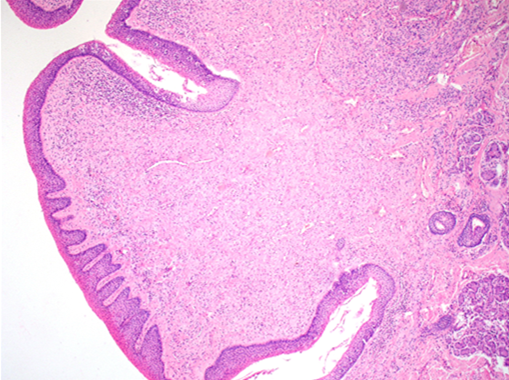

Question 1

Question

Label this image

Image:

8bf7aa50-9d64-4e14-9bf0-b04b9cbcbdea (image/jpeg)

Answer

Lips